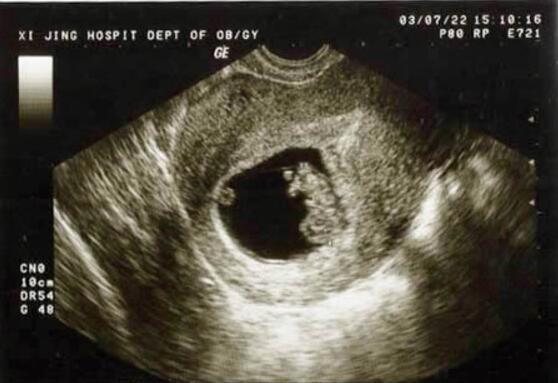

医生给她检查后大吃一惊,因为小果的子宫里并没有胎儿,这个已经7个多月的胎儿竟然在她的腹腔内。医生都表示这么大月份的宫外孕还是头一次见,通常情况下宫外孕在40-50天的时候就会发现,最多的会拖到60天。这种宫外孕在孕妇体内就像一颗“定时炸弹”,随时会发生大出血。虽然二人只带了500元,但是救人要紧。医院的产科、妇科、放射科、麻醉科等专家对小果的情况进行了会诊,之后立即进行了手术。

开腹后发现,她的肚子里有一个大包块贴着腹腔后壁,包块里充满了血水和血凝块,在血水中间,羊膜包着一个小小的胎儿,已经死亡了。经过医生的奋力抢救,小果脱离了生命危险,但是后续的治疗还没有结束。医生说,其实只要小果在孕早期去做一下产检就会发现宫外孕,也不至于导致现在这样严重的后果。而男友却说,他们身边的朋友生了好几个都没有产检过,他们才不会花那冤枉钱呢。医生听后气的直想掀桌子。